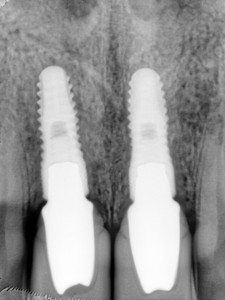

김정아 앞니 치료후 PA

앞니 임플란트 2개를 식립하고 최종 보철물 까지 올린 작은 방사선 사진입니다.

앞니 임플란트 2개가 잇몸뼈에 잘 식립된 것을 확인할 수 있습니다.